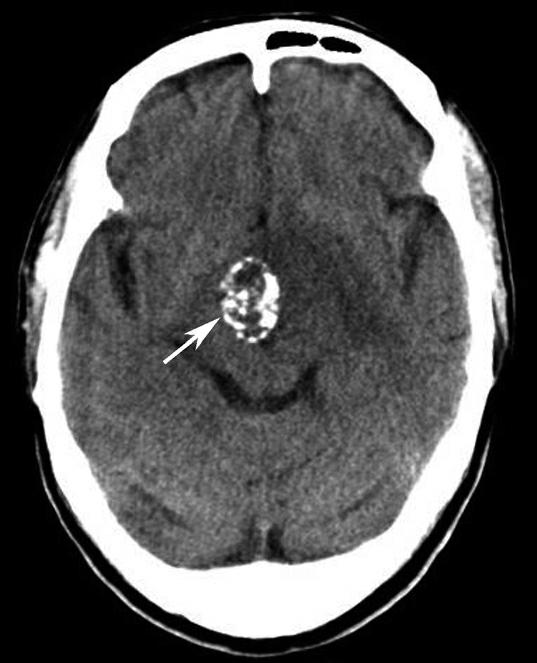

破裂孔、卵圆孔、棘孔及斜坡等均为重要的解剖结构,临床常见疾病如鼻咽癌常侵犯上述结构(图1-2-3)。颈静脉孔区较常见的肿瘤为颈静脉球瘤,常伴有颈静脉孔及其邻近骨质的破坏(图1-2-4)。

图1-2-3 鼻咽癌颅底骨质破坏

A.横断面;B.横断面(骨窗)

骨窗示左侧岩尖、斜坡、左侧蝶骨大翼骨质破坏、受侵(白箭),肿瘤经破裂孔侵入颅内(黑箭头)